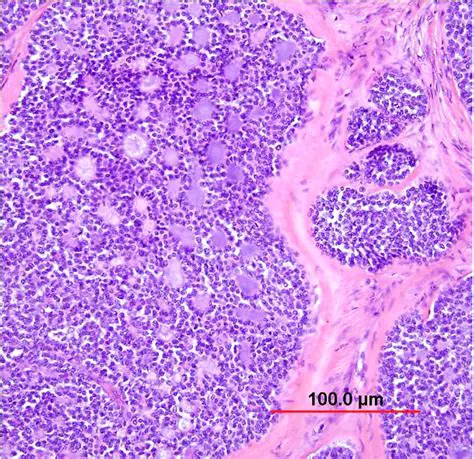

Invasive Cervical Carcinoma